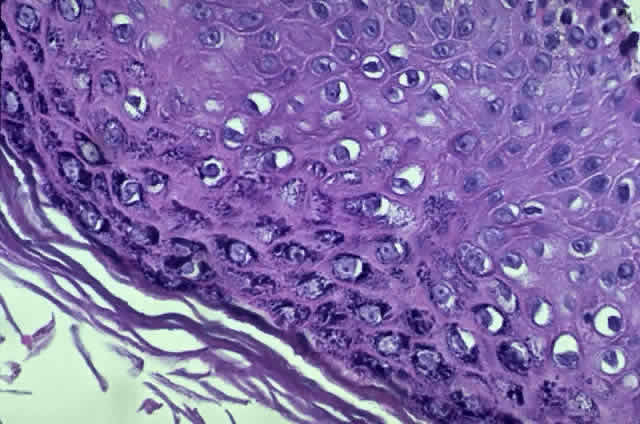

HPV-induced conjunctival squamous papillomas demonstrate papillomatosis, acanthosis, and koilocytosis (Fig. 6). Because they are mucous membrane lesions, those of the conjunctiva and lacrimal sac show no granular cell layer but will show keratinization if they are large or exposed (Fig. 7). In our experience the frequency of koilocytes is variable, even in lesions almost certain to be viral (Fig. 8). Scattered inflammatory cells may be present in the cores or epithelium. Virus can be detected immunohistochemically in the nuclei of the cells (Fig. 9).

Historically, viral involvement was indicated by the presence of koilocytosis. Later, immunohistochemical analysis of HPV-common antigens allowed the first demonstration of viral components in lesional cells (see Fig. 8). Newer, more specific DNA-based techniques allowed typing of viruses. In situ hybridization, which bridged DNA and immunohistochemical techniques, was somewhat more sensitive than either technique alone. The development of PCR amplification allowed detection of a tiny amount of original source DNA and, with proper controls, powerful statements could be made about specific virus involvement. Because DNA is relatively stable compared to many antigens, DNA techniques can be used on archival material or on specimens fixed with aldehydes and embedded in paraffin.